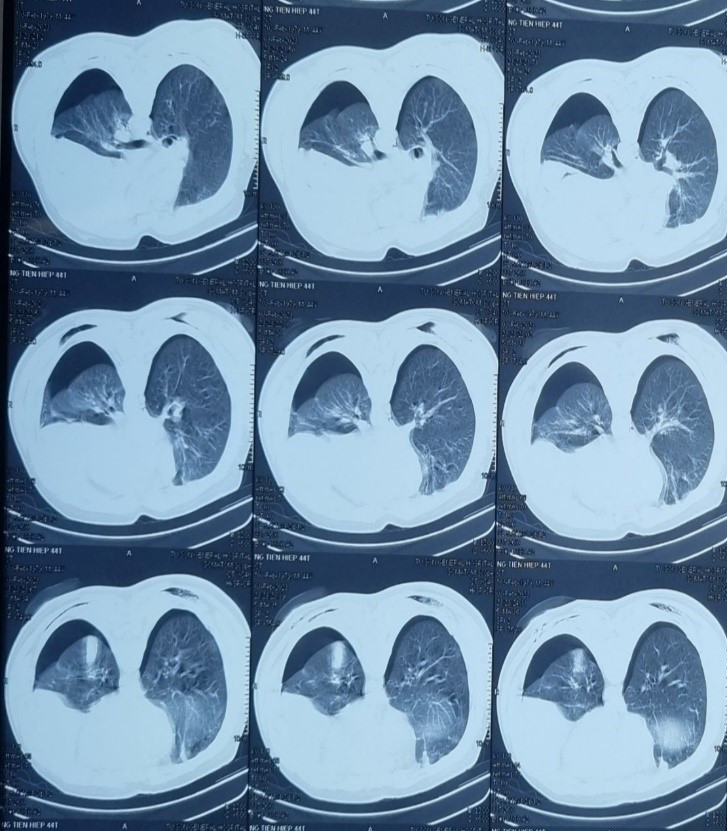

Bệnh nhân vào cấp cứu giờ thứ 2 sau tai nạn trong tình trạng lơ mơ, da niêm mạc nhợt, khó thở, mạch nhanh nhỏ. Kết quả chụp cắt lớp vi tính cho thấy lồng ngực tràn khí - tràn dịch khoang màng phổi trái mức độ nhiều, tràn khí màng phổi phải. Các bác sĩ xác định đây là tình trạng nguy hiểm, có thể sốc không hồi phục nếu không được xử trí sớm.